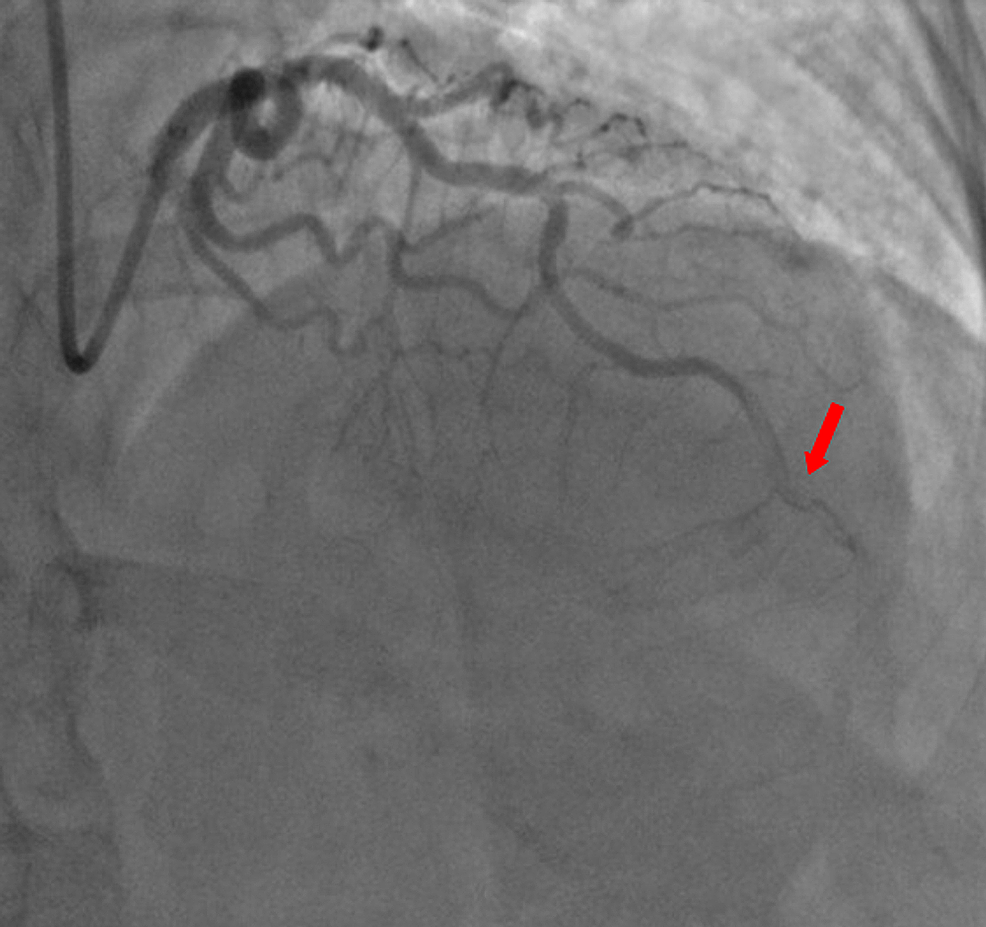

A 59-year-old woman was admitted to the emergency department with sudden onset of chest pain for five hours. She had hypertension (treated with β-blockers) as a cardiovascular risk factor. She was diagnosed with advanced non-small-cell lung cancer with liver metastases one month previously. The patient was not considered for surgical resection, she was scheduled for chemotherapy, and, consequently, no antineoplastic treatment had been initiated yet. Prophylactic anticoagulation was not indicated On clinical examination, her blood pressure was 150/90 mmHg with a pulse of 100 beats per minute, oxygen saturation of 95%, and normal heart sounds. The 12-lead electrocardiogram showed sinus rhythm with a heart rate of 102 beats for minutes and ST-segment elevation in all leads except aVR where ST-segment depression was noted (Figure 1). Her laboratory test results revealed a baseline troponin T level of 1212 ng/ml (normal range < 26 ng/ml). Also, the echocardiography findings revealed akinetic walls from the mid to apical septum and anterior and inferior walls. The ejection fraction was estimated to be 39%. Therapy was started with clopidogrel, aspirin, and low-molecular-weight heparin. The patient underwent a coronary angiogram from the right radial approach, which revealed the presence of an extended thrombus in the left anterior descending artery (LAD), and another thrombus was found in the second segment of the right coronary artery (RCA) with thrombolysis in myocardial ischemia (TIMI) III flow and without any atherosclerotic lesions in the coronary artery tree (Figure 2 and Figure 3), therefore, balloon angioplasty and/or stent placement was not considered. The patient was taken to the coronary care unit (CCU) and tirofiban infusion was administered for a period of 48 hours. In view of persistent breathlessness, pulmonary embolism was suspected. There were no symptoms or clinical signs suggestive of deep venous thrombosis. A computed tomographic pulmonary angiography was performed and showed a distal pulmonary embolism (Figure 4). The patient was discharged on acenocoumarol to be followed as an outpatient. At her 45 days follow-up, she did not report any episode of chest pain, bleeding, as well as any thrombotic events.

Malignancy is a recognized risk factor for deep vein thrombosis, pulmonary embolism, and even arterial thromboembolism, including peripheral thrombosis, stroke, and myocardial infarction [3]. Thrombosis represents the second most common cause of death in cancer patients [4]. Several determinants are considered to participate in hypercoagulability in malignancy. The secretion of pro-inflammatory cytokines and pro-coagulants from neoplastic cells causes endothelial damage in many vascular territories. The consequence is upraised vascular permeability for platelet-activating factors and tissue factors, decreased inhibitors of coag­ulation, and impaired fibrinolysis, which increase the risk of thrombosis [5-6]. The present case describes a rare case of intracoronary thrombosis in a 59-year-old woman recently diagnosed with lung cancer. The coronary angiography had not revealed any significant coronary stenosis in the entire coronary artery tree. It is reasonable that the hypercoagulable state of cancer was responsible for intracoronary thrombosis. This is consistent with a few previously reported cases.